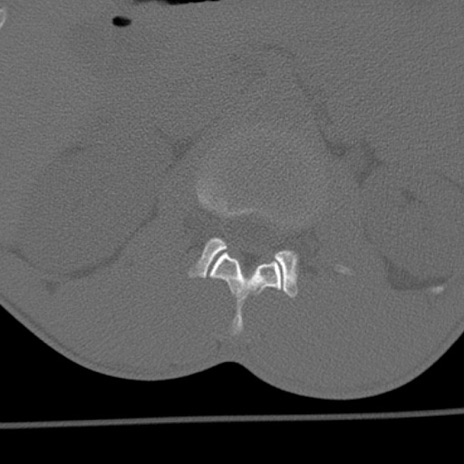

症例3 腰椎CT(横断像)

腰椎CT